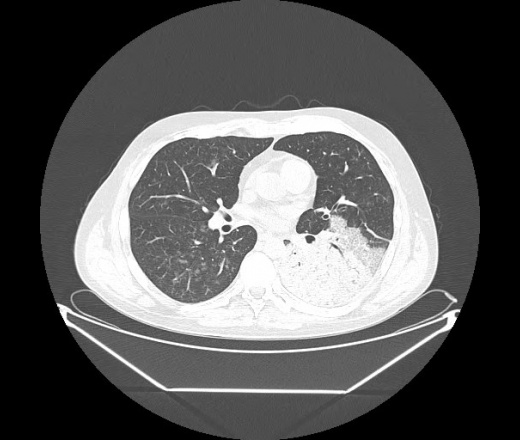

М. 1984 г.р.  Лихорадка 39, кашель , одышка.. и надоевший всем вопрос- "типично ли для ковид?" ( в настоящее время на него обязательно нужно дать ответ в своем протоколе)

На мой взгляд нетипично для ковид: много центрально-расположенных поражений, лобарное поражение нижней доли слева. 50/50

Не типичая картина для ковид.

КТ-признаки двусторонней бактериальной пневмонии.

Все верно, здесь абсолютно нетипичная картина, несмотря на матовое стекло с ретикулярными изменениями, но почему-то  посчитали иначе. Кстати,  "малыша" не заметили)?

Добавил 6 день

Что за малыш? Будущий абсцесс? Не заметил. Только о туберкулёзе подумал

+ 1?  Зона очень похожа была на формирующийся абсцесс, даже по рентгенпризнакам. Еще хотела спросить, но постеснялась. А на контроле видно

да, это я о абсцессе.